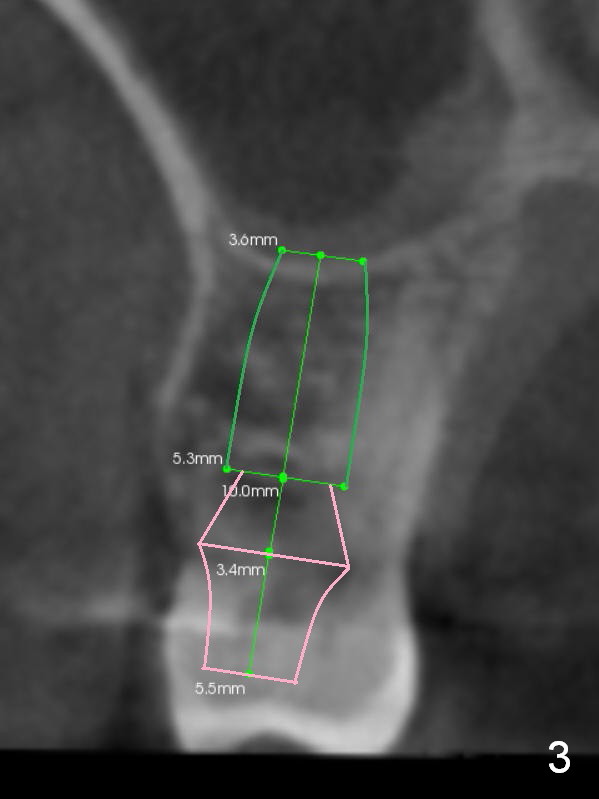

In addition to supraeruption of the teeth #2 and 3, the caries in the mesiobuccal root of #3 seems to be beyond salvation (Fig.1,2 arrowhead). When the implant at #3 is osteointegrated, a provisional restoration is placed (Fig.4 pink). Brackets (white boxes) are placed at differential levels among #1-3 to initiate regional orthodontic treatment using #3 as an anchorage. Mini-implants are placed if necessary. The tooth #1 is extracted after the limited ortho. Scaling & root planing will be done first.

Re-examination clinically and radiologically reveals that there is no caries involving the tooth #3 (Fig.5). It appears that CBCT may have artifact. Treatment planning for intrusion should be modified. Mini-implants will be employed after #2 DO composite. Prepare Anchor mini-implant kit, 2 of 10 mm and 1 of 8 mm mini-implants, anesthetics and #15 scalpel. Scaling & root planing will be performed.